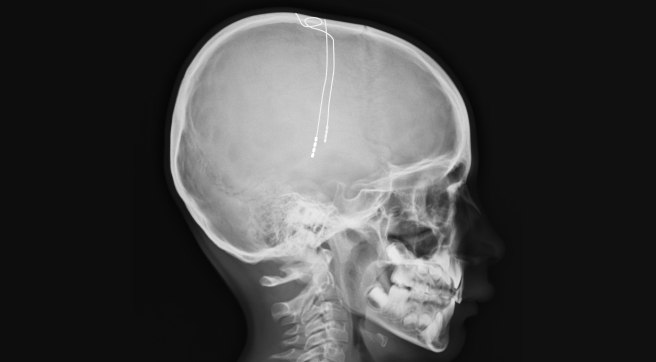

- New study finds MR-guided focused ultrasound blood brain barrier opening of the nigrostriatal system is a feasible & well-tolerated approach in 3 patients with Parkinson’s; Pilot data could “facilitate delivery of putative neurorestorative molecules” (Click here to read more about this).